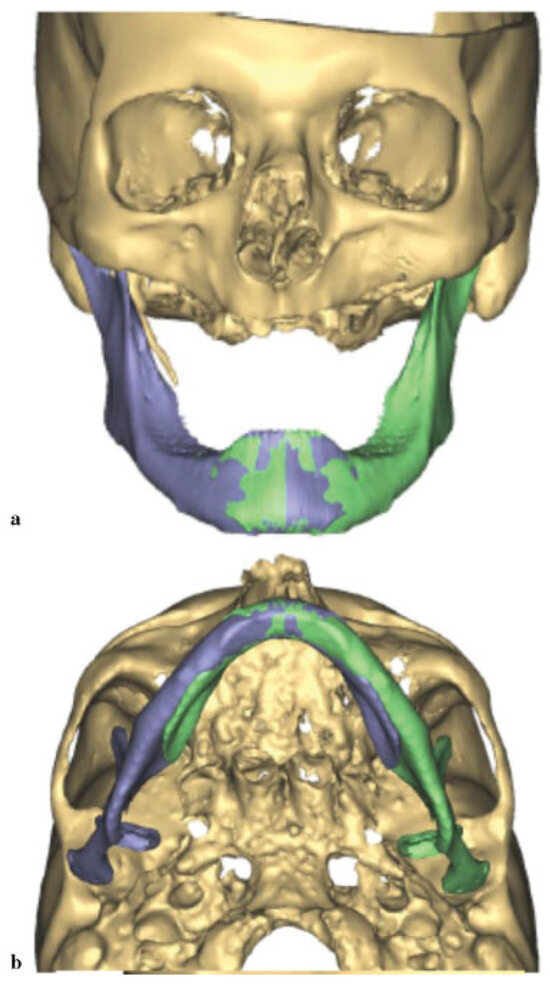

Prior to surgery, VSP was implemented to plan the procedure (Materialize, Plymouth, MI). A CBCT was obtained. Similar to the previous case, the midline of the major segment was aligned with the midline of the maxilla (Figure 7a,b). The displaced smaller segment was placed in the glenoid fossa and the inferior borders were aligned. A mirror image of the unaffected right side of the mandible was then superimposed. The area of lytic bone was outlined and a model was fabricated. A 2.5-mm locking reconstruction plate was prebent according to the 3D model using the mirror image model with enough length to span the area that would be reconstructed (Figure 8).

Figure 7. (a) Displacement of the jaw prior to manipulation. (b) Alignment of the midline of the mandible with the maxilla revealing the large defect on the jaw lateral border.